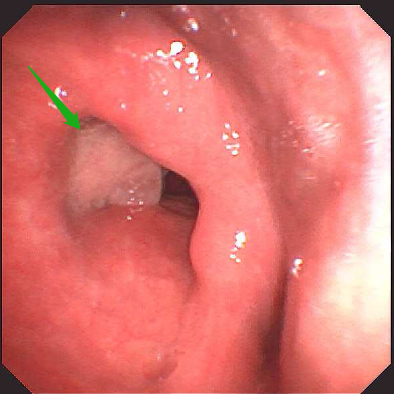

今年 60 岁的张大叔(化名)半年前突然感到声音嘶哑,说话费力。想着自已平日身体硬朗便完全没放在心上,抽烟饮酒也一如既往,直至声音越来越哑、吐词不清,感觉都不是自己在说话,到当地医院检查后,纤维喉镜发现,张大叔的喉腔右侧室带、声带新生物样隆起,表面粘膜不平整,且右侧声带完全固定。

医生考虑喉新生物为恶性肿瘤,已经到了中晚期,建议先活检,再全喉切除。但张大叔平日里喜欢与朋友畅谈,不肯切全喉,家里的亲戚轮番来劝。耳鼻咽喉头颈外科刘蓉蓉主任、姬长友教授接诊后,立刻完善颈部 CT,显示 1. 右侧室带及声带增厚伴软组织结节形成,考虑新生物,建议病理组织学检查 2. 颈部少许小淋巴结。